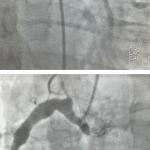

Syndrome coronarien aigu avec sus-décalage du segment ST

Un homme de 32 ans consulte pour un malaise sans prodrome et sans perte de connaissance survenu quinze minutes...